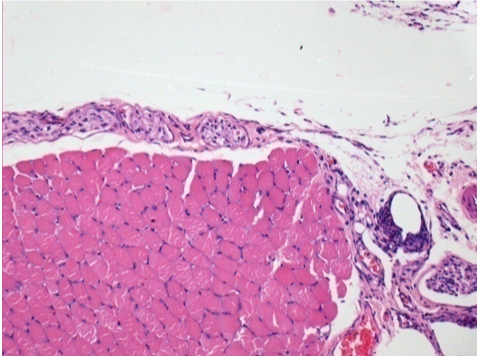

0.5 ml ( 5x 0.1ml) Endopeel SC Injection in the right subcutaneous pretibial area.

L:200x-Control-SC

R-D10-SC-200X